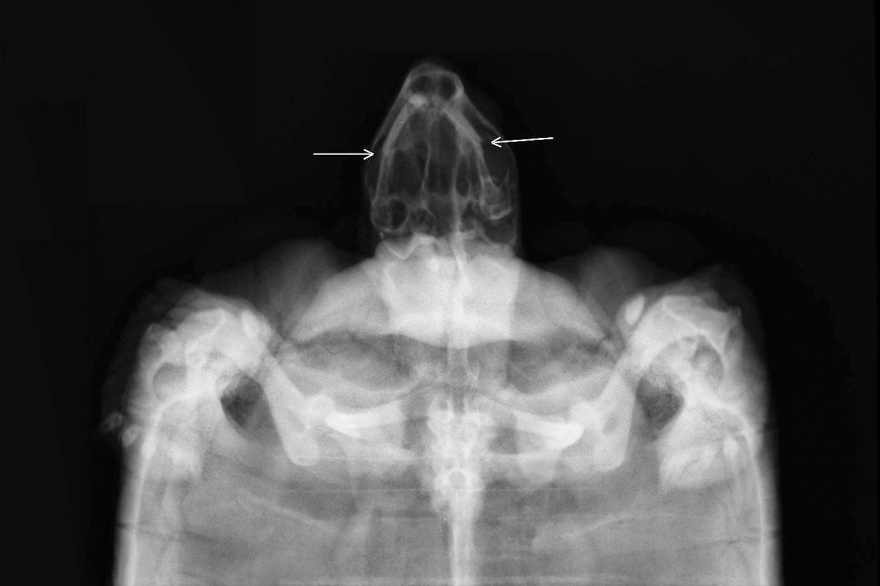

En las mismas se observa fractura del tercio medio de ambas caras mandibulares con leve desplazamiento de cabos hacia lateral.